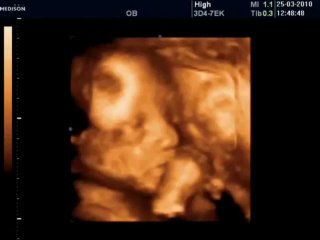

BCF Ultrason Görüntüsü - Hasvet Medikal